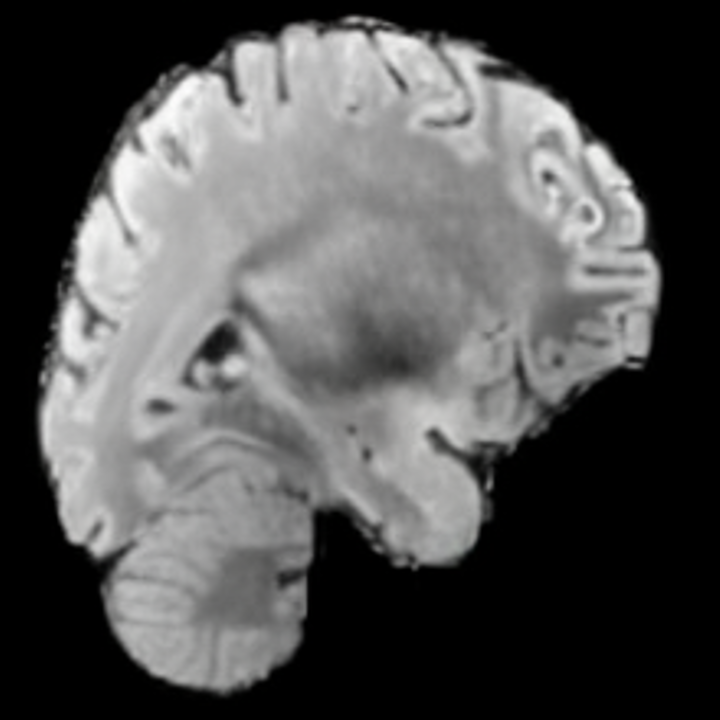

Preservation of Spine Curvature. For the spine segmentation on UK Biobank, we use a UNet++ model [83] with Dice Loss. We use a model trained to predict curves on DXA on UK Biobank [11]). We measure the Pearson correlation factor [11] of spine curvature measured on the generated MRIs where the input is a single MRI coronal slice, a single sagittal slice, or from the paired DXA, against the curvature of reference real MRIs of the same samples. The correlation coefficients are 0.89 for the coronal MRIs, 0.88 for the sagittal MRIs, and 0.87 for the DXAs on the test set of 308 human-annotated angles. We can then bin the curvature of the spines under different scoliosis categories based on human-annotated angles: mild: , moderate: , and severe . We show the results in Figure 8. This illustrates that the generated MRIs preserve the spine curvature from normal to severe scoliosis cases. Additional details about spine curvature are provided in supplementary material.

For the spine segmentation on UK Biobank, we use a UNet++ model [83] with Dice Loss. We use a model trained to predict curves on DXA on UK Biobank [11]. We show in Figure IX that generated MRIs preserve the spine curvature from normal to severe scoliosis cases. We also study the case when DXA is used to generate the MRIs and show in Figure IX how the correlation to real curvatures compares to the input MRI case. The curvatures of the MRI generated from the coronal plane match the DXA curvatures more than the curvatures generated from sagittal MRI. This is expected since the antero-posterior plane of DXA is equivalent to the coronal plane for MRIs. This also explains the greater Pearson’s correlation coefficient of the coronal MRI (0.89) and DXA-generated curvature (0.88) compared to sagittal-generated curvature (0.87) relative to the reference curvature on the coronal plane. We observe though that MRI generation using X-Diffusion from another plane than the conventional plane for scoliosis assessment is valid.